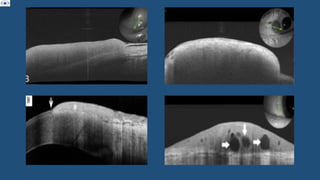

• AS - OCT :

• AS -OCT :